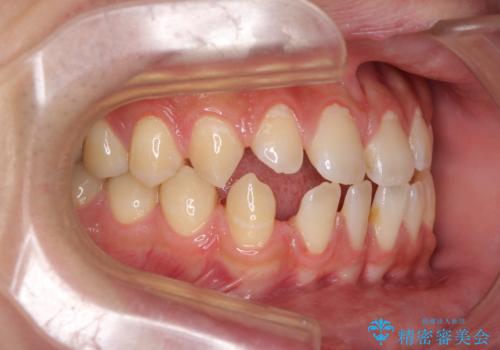

- 上下前歯の隙間を気にして来院された患者様です。

飲み込みや話をするときに舌を突出させる癖が強くあり、それが原因でスペースが空いていました。

舌癖を改善するためのトレーニングを行いながら、ワイヤー装置を用いて前歯の隙間を閉じていくこととしました。